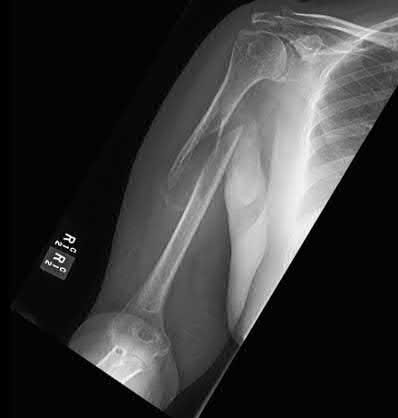

Question 12:

A 55-year-old patient presents with a slowly enlarging, painful mass in the proximal humerus. Biopsy reveals a hyaline cartilage matrix with cellular atypia, confirming a diagnosis of central conventional chondrosarcoma. Which of the following genetic mutations is most frequently identified in this specific tumor?

Correct Answer: IDH1 / IDH2

Explanation:

Mutations in the isocitrate dehydrogenase genes, IDH1 and IDH2, are found in up to 50-60% of central conventional chondrosarcomas and enchondromas. EXT1 and EXT2 mutations are characteristic of multiple hereditary exostoses (osteochondromas). GNAS mutations are seen in fibrous dysplasia. TP53 and RB1 mutations are hallmark aberrations in osteosarcoma.